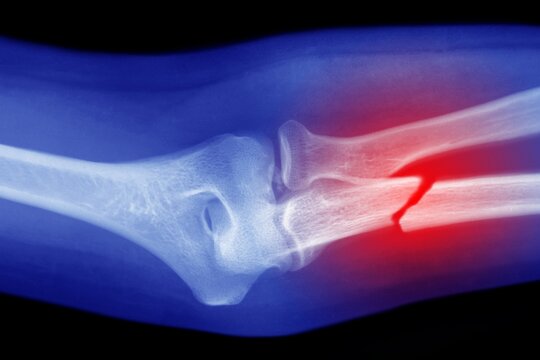

• Knochenbrüche